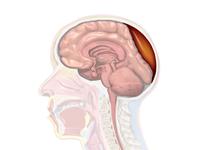

Epidural hematoma as seen on a CT scan with overlying skull fracture. Note the biconvex shaped collection of blood. There is also bruising with bleeding on the opposite side of the brain.

Epidural hematoma is when bleeding occurs between the tough outer membrane covering the brain (dura mater) and the skull.[4] Often there is loss of consciousness following a head injury, a brief regaining of consciousness, and then loss of consciousness again.[2] Other symptoms may include headache, confusion, vomiting, and an inability to move parts of the body.[1] Complications may include seizures.[1]

Epidural hematomas usually appear convex in shape because their expansion stops at the skull's sutures, where the dura mater is tightly attached to the skull. Thus, they expand inward toward the brain rather than along the inside of the skull, as occurs in subdural hematomas. Most people also have a skull fracture.[3]